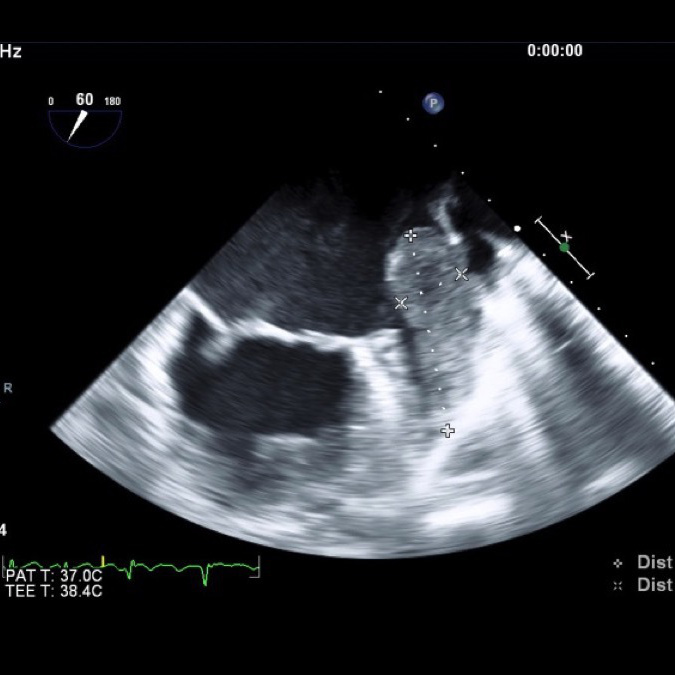

経食道心エコー図検査

我々は経胸壁心エコー図検査のほかに経食道心エコー図検査も多くの件数を行っております。心腔内血栓や弁膜症、先天性心疾患、感染性心内膜炎などの疾患を詳細に評価するには胸壁からの観察では不十分なことが多くあります。より正確に評価するための手段の一つとして心臓の奥にある食道から心臓を観察する経食道エコー検査が用いられています(図2)。この検査により、治療方針、手術適応の有無などをしっかり評価することができ、心臓血管外科とスムーズに連携して治療をおこなっています。